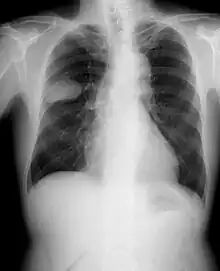

Small-cell lung cancer

Lung cancer is the leading cause of cancer-related deaths worldwide, accounting for the highest mortality rates among both men and women. When associated with the lung, SCLC is sometimes called "oat cell carcinoma" due to the flat cell shape and scanty cytoplasm. Caution is required when diagnosing SCLC because small cell mesothelioma – an extremely rare subtype of lung cancer – can be mistaken for small cell lung cancer.[23]